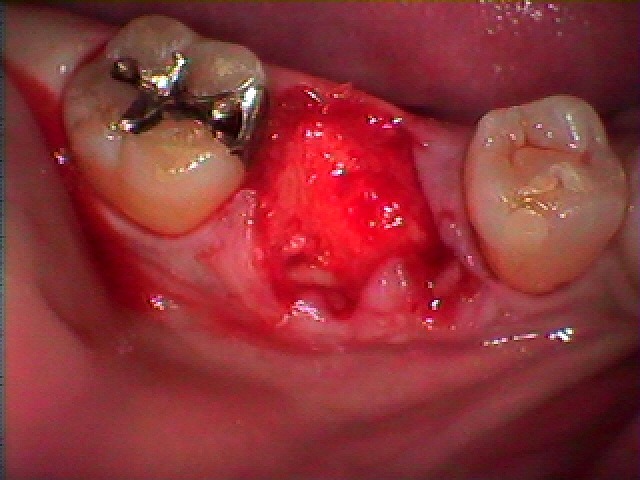

レントゲンもとりましたが確かに抜歯の歯でした

歯を抜かせていただきました